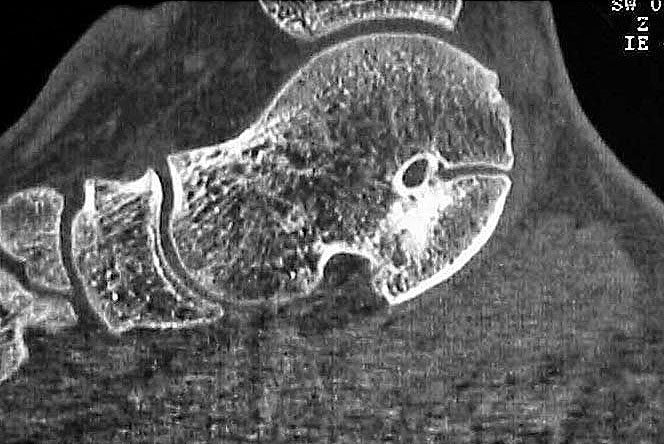

MRT und CT konkurrieren in der Fein-Darstellung der Knochenbrücke, der Beurteilung der nichtbetroffenen Anteile des Subtalargelenkes und der Sekundärveränderungen. Das MRT bietet den Vorzug, bindegewebige und knorpelige Strukturen (Abb. 2) und bei Einsatz von Kontrastmittel auch knöcherne Aktivierungsphänomene genau abzubilden; die knöcherne Feinstruktur und genaue Ausdehnung dagegen ist mit dem Dünnschicht-CT wesentlich exakter darstellbar (Abb.3). In manchen Fällen ist eine 3-D-Rekonstruktion des CT hilfreich. Besonders wichtig ist eine geeignete Schichtebenen-Wahl:

Diagnostisch sollte neben Röntgenübersichtsaufnahmen (indirekte radiologische Zeichen: Dorsaler Traktions-Osteophyt am Taluskopf, „talar beaking“; kontinuierliche Linie der Trochlea-tali-Kontur übergehend in die Sustentaculum-tali-Kontur, „C-Zeichen“ (Abb. 11) 10) immer die dreidimensionale Bildgebung eingesetzt werden. Das MRT (mit Kontrastmittel) kann die Struktur der Brückenbildung und z.B. die Qualität des Restgelenkes (Knorpel-Dicke) besonders gut abbilden; das Dünnschicht-CT zeigt die knöcherne Feinstruktur im Bereich der Coalitio und den oft sehr schrägen Spalt-Verlauf im Frontalschnitt dagegen häufig genauer. Meist findet sich die Überbrückung im Bereich der medialen Facette; die Schichten sollten jedoch bis weit nach dorsal beurteilt werden, da ansonsten dorsomediale Formen übersehen werden können. Rozansky et al 7 unterschieden fünf morphologische Typen auf der Basis von 3-D-CT-Rekonstruktionen. Allerdings ist eine prognostische Zuordnung bisher nicht möglich.